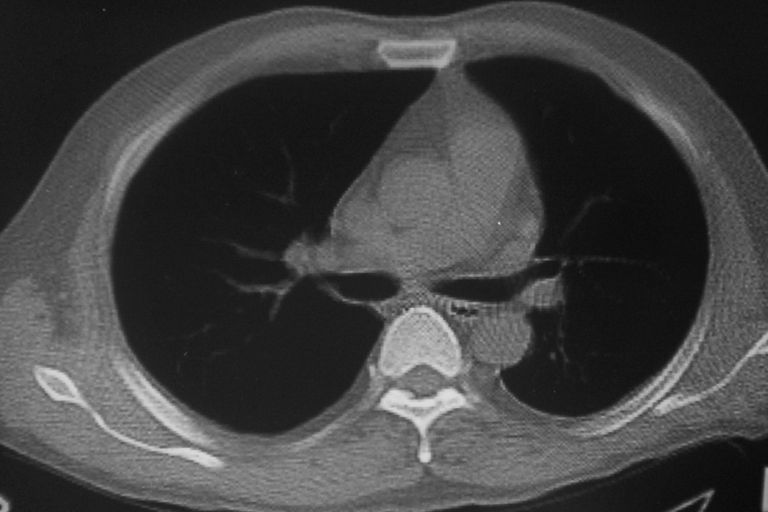

患者 男 50岁 无痛性咯血3天,无其他不适.

左下肺结节状软组织密度影,边缘有毛刺,考虑周围型肺癌。

1 左肺下叶基底段见两结节软组织密度灶, 肺窗边缘见有毛刺征像, 不能排除占位. 2 建议结合临床治疗一周后ct随访在看其结果.

临近胸膜增厚,病变周围肺不清,稍有分叶。结节密度略高,肺、纵隔窗差异不大,肺癌待排。前方还有一个

左下肺结节状软组织密度影,一个边缘有卫星病灶,邻近胸膜增厚.另一个有毛刺.心影周围水样密度影环绕.考虑:

1.肺癌可能.肺tb待排.

2.左侧胸膜增厚.心包积液.